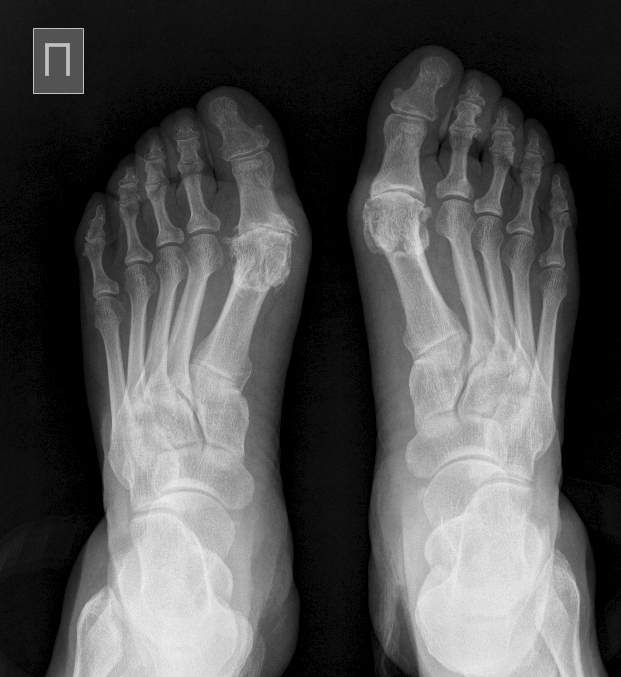

Hallux rigidus+Hallux valgus: интересно мнение коллег

Уважаемые коллеги, интересно Ваше мнение по поводу данной деформации. Пациентку беспокоит боль в обеих стопах, часто по ночам.

Хоть бы возраст указали. Да и профессию, заодно. Если пожилого возраста полная повариха - так отчего же по ночам стопам не болеть при таком артрозе. Или молодая оффисная работница, добирающаяся до работы из далекого подмосковья в часы пик с пересадками в модельной обуви. А если серьезно - артроз первых плюснефаланговых суставов вполне объясняется врожденной особенностью стоп в виде преобладания длин первых плюсневых. А вот изменения в межфаланговых суставах латеральных пальцев непонятны. Или это полиостоартроз. Тогда опять возраст нужен, снимки кистей. Или полиартропатия. Тогда искать системное воспалительное заболевание.

Возраст 63 года, лишний вес присутствует.Системного заболевания нет. Боль по ночам не основная проблема, я некорректно описал симптомы: боль беспокоит в основном при ходьбе, причем больше слева. Но ночью пациентка временами не может уснуть. Ортопедические стельки носит, но без выраженного эффекта. Вопрос надо ли восстанавливать правильное положение 1го луча на правой стопе или просто сделать артродез? Вопрос ношения обуви на высоком каблуке для нее не стоит. И что бы Вы сделали с левой стопой?

Все-таки остается много непонятного. Вы спрашиваете, нужна ли коррекция 1 луча. Но по представленным снимкам невозможно точно судить о величине 1 межплюсневого угла. Хотя, подвывиха сесамовидных нет, значит угол нормальный. В такой ситуации планировать остеотомию scarf - стрелять из пушки по воробьям. Укорочения 1 плюсневой можно добиться и шевронной и Вейль остеотомиями. Намного менее травматично и дешевле (1 винт). Если же речь идет только об отклонении кнаружи 1 пальца, так его можно исправить в любой момент, хоть при выполнении артродеза за счет обработки под нужным углом основания основной фаланги или путем корригирующей остеотомии, если будет избрана другая тактика. Но Вы ведь не описываете что именно болит в стопе. 1 плюснефаланговый? Или есть симптомы центральной метатарсалгии? Или недостаточности 2 луча? Периостальный слой на 2 плюсневой левой стопы значимо толще, чем на 2 плюсневой справа. Это говорит о ее функциональной перегрузке. При этом ее относительная длина также больше слева. Есть ли натоптыш под ее головкой или симптомы нестабильности 2 плюснефалангового сустава? Ведь если боли связаны со 2 лучом, укорочение 1 плюсневой только усугубит ситуацию. Получается, что мы никак не можем объяснить сейчас, почему слева болит больше. И при таких начальных симтомах артроза слева идти на артродез... Может подавать НПВС, сделать блокаду с дексаметазоном, провести курс физиотерапии?